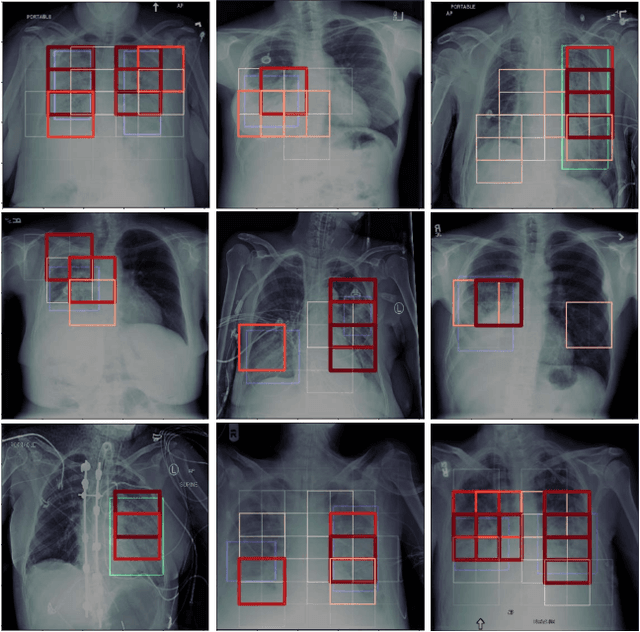

Abstract:The automatic detection of critical findings in chest X-rays (CXR), such as pneumothorax, is important for assisting radiologists in their clinical workflow like triaging time-sensitive cases and screening for incidental findings. While deep learning (DL) models has become a promising predictive technology with near-human accuracy, they commonly suffer from a lack of explainability, which is an important aspect for clinical deployment of DL models in the highly regulated healthcare industry. For example, localizing critical findings in an image is useful for explaining the predictions of DL classification algorithms. While there have been a host of joint classification and localization methods for computer vision, the state-of-the-art DL models require locally annotated training data in the form of pixel level labels or bounding box coordinates. In the medical domain, this requires an expensive amount of manual annotation by medical experts for each critical finding. This requirement becomes a major barrier for training models that can rapidly scale to various findings. In this work, we address these shortcomings with an interpretable DL algorithm based on multi-instance learning that jointly classifies and localizes critical findings in CXR without the need for local annotations. We show competitive classification results on three different critical findings (pneumothorax, pneumonia, and pulmonary edema) from three different CXR datasets.

Abstract:Pneumothorax is a critical condition that requires timely communication and immediate action. In order to prevent significant morbidity or patient death, early detection is crucial. For the task of pneumothorax detection, we study the characteristics of three different deep learning techniques: (i) convolutional neural networks, (ii) multiple-instance learning, and (iii) fully convolutional networks. We perform a five-fold cross-validation on a dataset consisting of 1003 chest X-ray images. ROC analysis yields AUCs of 0.96, 0.93, and 0.92 for the three methods, respectively. We review the classification and localization performance of these approaches as well as an ensemble of the three aforementioned techniques.